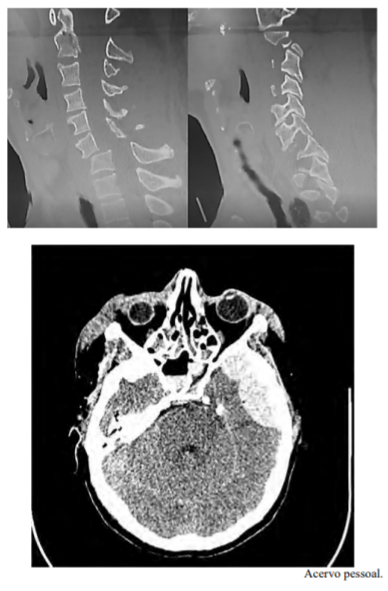

Uma paciente de 27 anos de idade, com 63 kg, previamente hígida, é levada ao hospital pelos bombeiros, em imobilização padrão, após colisão do próprio carro em uma árvore. Queixa-se de cefaleia, cervicalgia e desconforto em ombros/membros superiores. Ao exame inicial, constatam-se AC = RC2T com BNF; FC = 110 bpm; AP = MVF sem RA; FR = 18 irpm; PA = 140 mmHg x 90 mmHg; e SatO2 = 99%. Na avaliação inicial, apresenta abertura ocular espontânea, pupilas isofotorreagentes, com colar cervical, fala confusa, amnésia lacunar e dor à palpação da coluna cervical, obedecendo a comandos, porém com dificuldade de mobilizar braços (força distal 1 e força proximal 4, em ombro e braço direito, e grau 3 à esquerda), com força aparentemente preservada em pernas. É realizada a tomografia computadorizada (TC) de crânio e coluna cervical, segundo as imagens apresentadas.

A TC de controle pós-operatório deverá ser classificada como Marshall V.